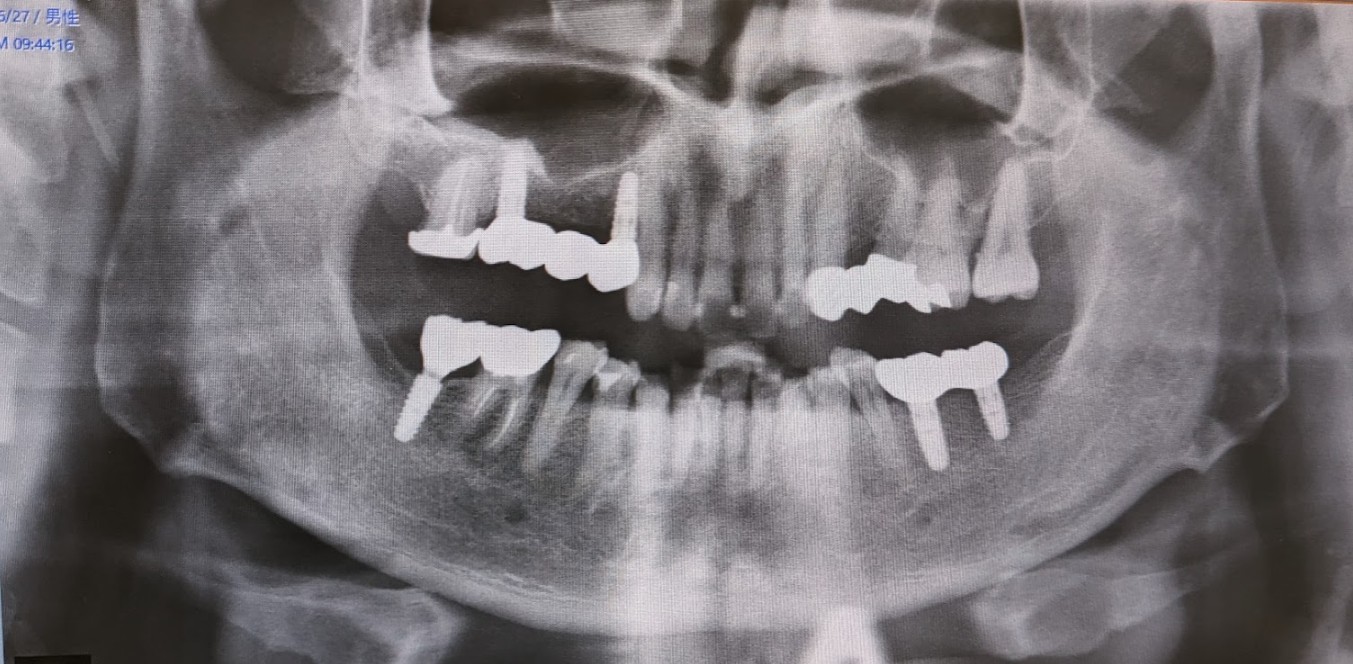

- 患者番号 = 2347 (2022-09-02 登録)

- 日程

- 2022-09-02 無料相談

- 2022-10-4 手術前検査

- 2022-10-25 オペ1 (右下奥歯、1本、通常手術)

- 2022-11-14 オペ2 (右上、3本ブリッジ、骨造成手術)

- 2023-01-25 頭出し1(右奥下)→ 合格

- 2023-02-15 頭出し2(右上)→ 合格

- 2023-03-07 型取り(右下、右上)

- 2023-03-31 右上、右下完成

- 2023-05-24 オペ3(左下)

- 2023-08-29 頭出し(右下2本)

- 2023-09-27 型取り(右下2本)

- 2023-10-30 左下2本 完成

- 2023-11-13 最終確認